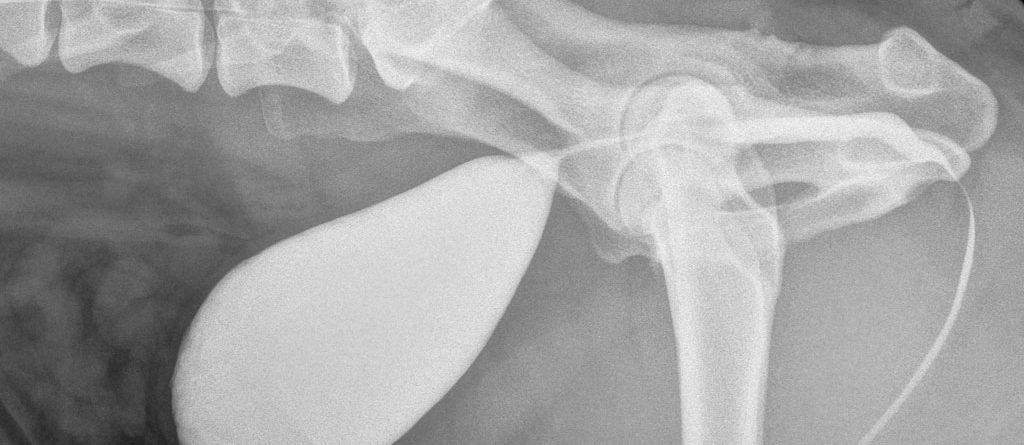

2 Aylık Dişi Melez Kedi

Anamnez 2 aylık dişi, melez kedinin; solunum güçlüğü, iştahsızlık şikayetleri vardır. Muayene Bulguları Fiziksel muayenede; hastada abdominal solunum mevcuttur....